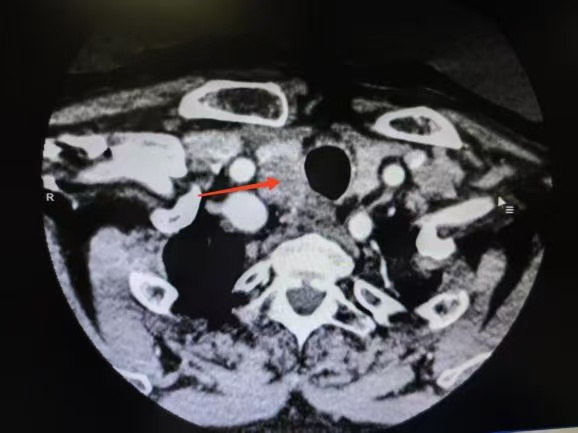

CT箭頭所示:側(cè)頸區(qū)轉(zhuǎn)移淋巴結(jié)

荊楚網(wǎng)(湖北日報網(wǎng))訊(通訊員 楊青青 沈浩元 )近日,孝感市中心醫(yī)院甲狀腺乳腺外科成功為一名67歲男性患者實施了高難度甲狀腺癌根治手術(shù)。該患者因頸部突發(fā)硬塊4天就診,經(jīng)檢查確診為雙側(cè)甲狀腺乳頭狀癌伴右頸側(cè)區(qū)多發(fā)淋巴結(jié)轉(zhuǎn)移,術(shù)中進一步發(fā)現(xiàn)腫瘤已侵犯包繞喉返神經(jīng),側(cè)區(qū)轉(zhuǎn)移淋巴結(jié)亦侵犯頸內(nèi)靜脈,病情復(fù)雜且兇險。

針對患者危急情況,甲狀腺乳腺外科迅速組建由沈浩元副主任醫(yī)師,楊青青主治醫(yī)師、王放明住院醫(yī)師的手術(shù)診療團隊。經(jīng)過4小時精細操作,團隊完整切除雙側(cè)甲狀腺及腫瘤,并完成中央?yún)^(qū)與頸側(cè)區(qū)淋巴結(jié)根治性清掃,成功保留了對發(fā)聲功能及血液循環(huán)至關(guān)重要的喉返神經(jīng)與頸內(nèi)靜脈。目前患者恢復(fù)順利,已轉(zhuǎn)危為安,診療效果得到患者及家屬認可。